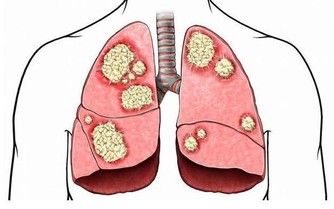

2.癌症

癌症也是這一年齡段高發的疾病,如肝癌、肺癌、乳腺癌、胃癌等。

癌組織侵犯血管或癌組織小血管破裂而產生。如肺癌患者可能咯血或痰中帶血;胃癌、食管癌、結腸癌則可能嘔血或便血,子宮頸癌可能有陰道流血。

CT檢查分辨率高,顯像清楚,可以在無症狀情況下發現某些特定器官的早期腫瘤,如肺癌的早期篩查等。